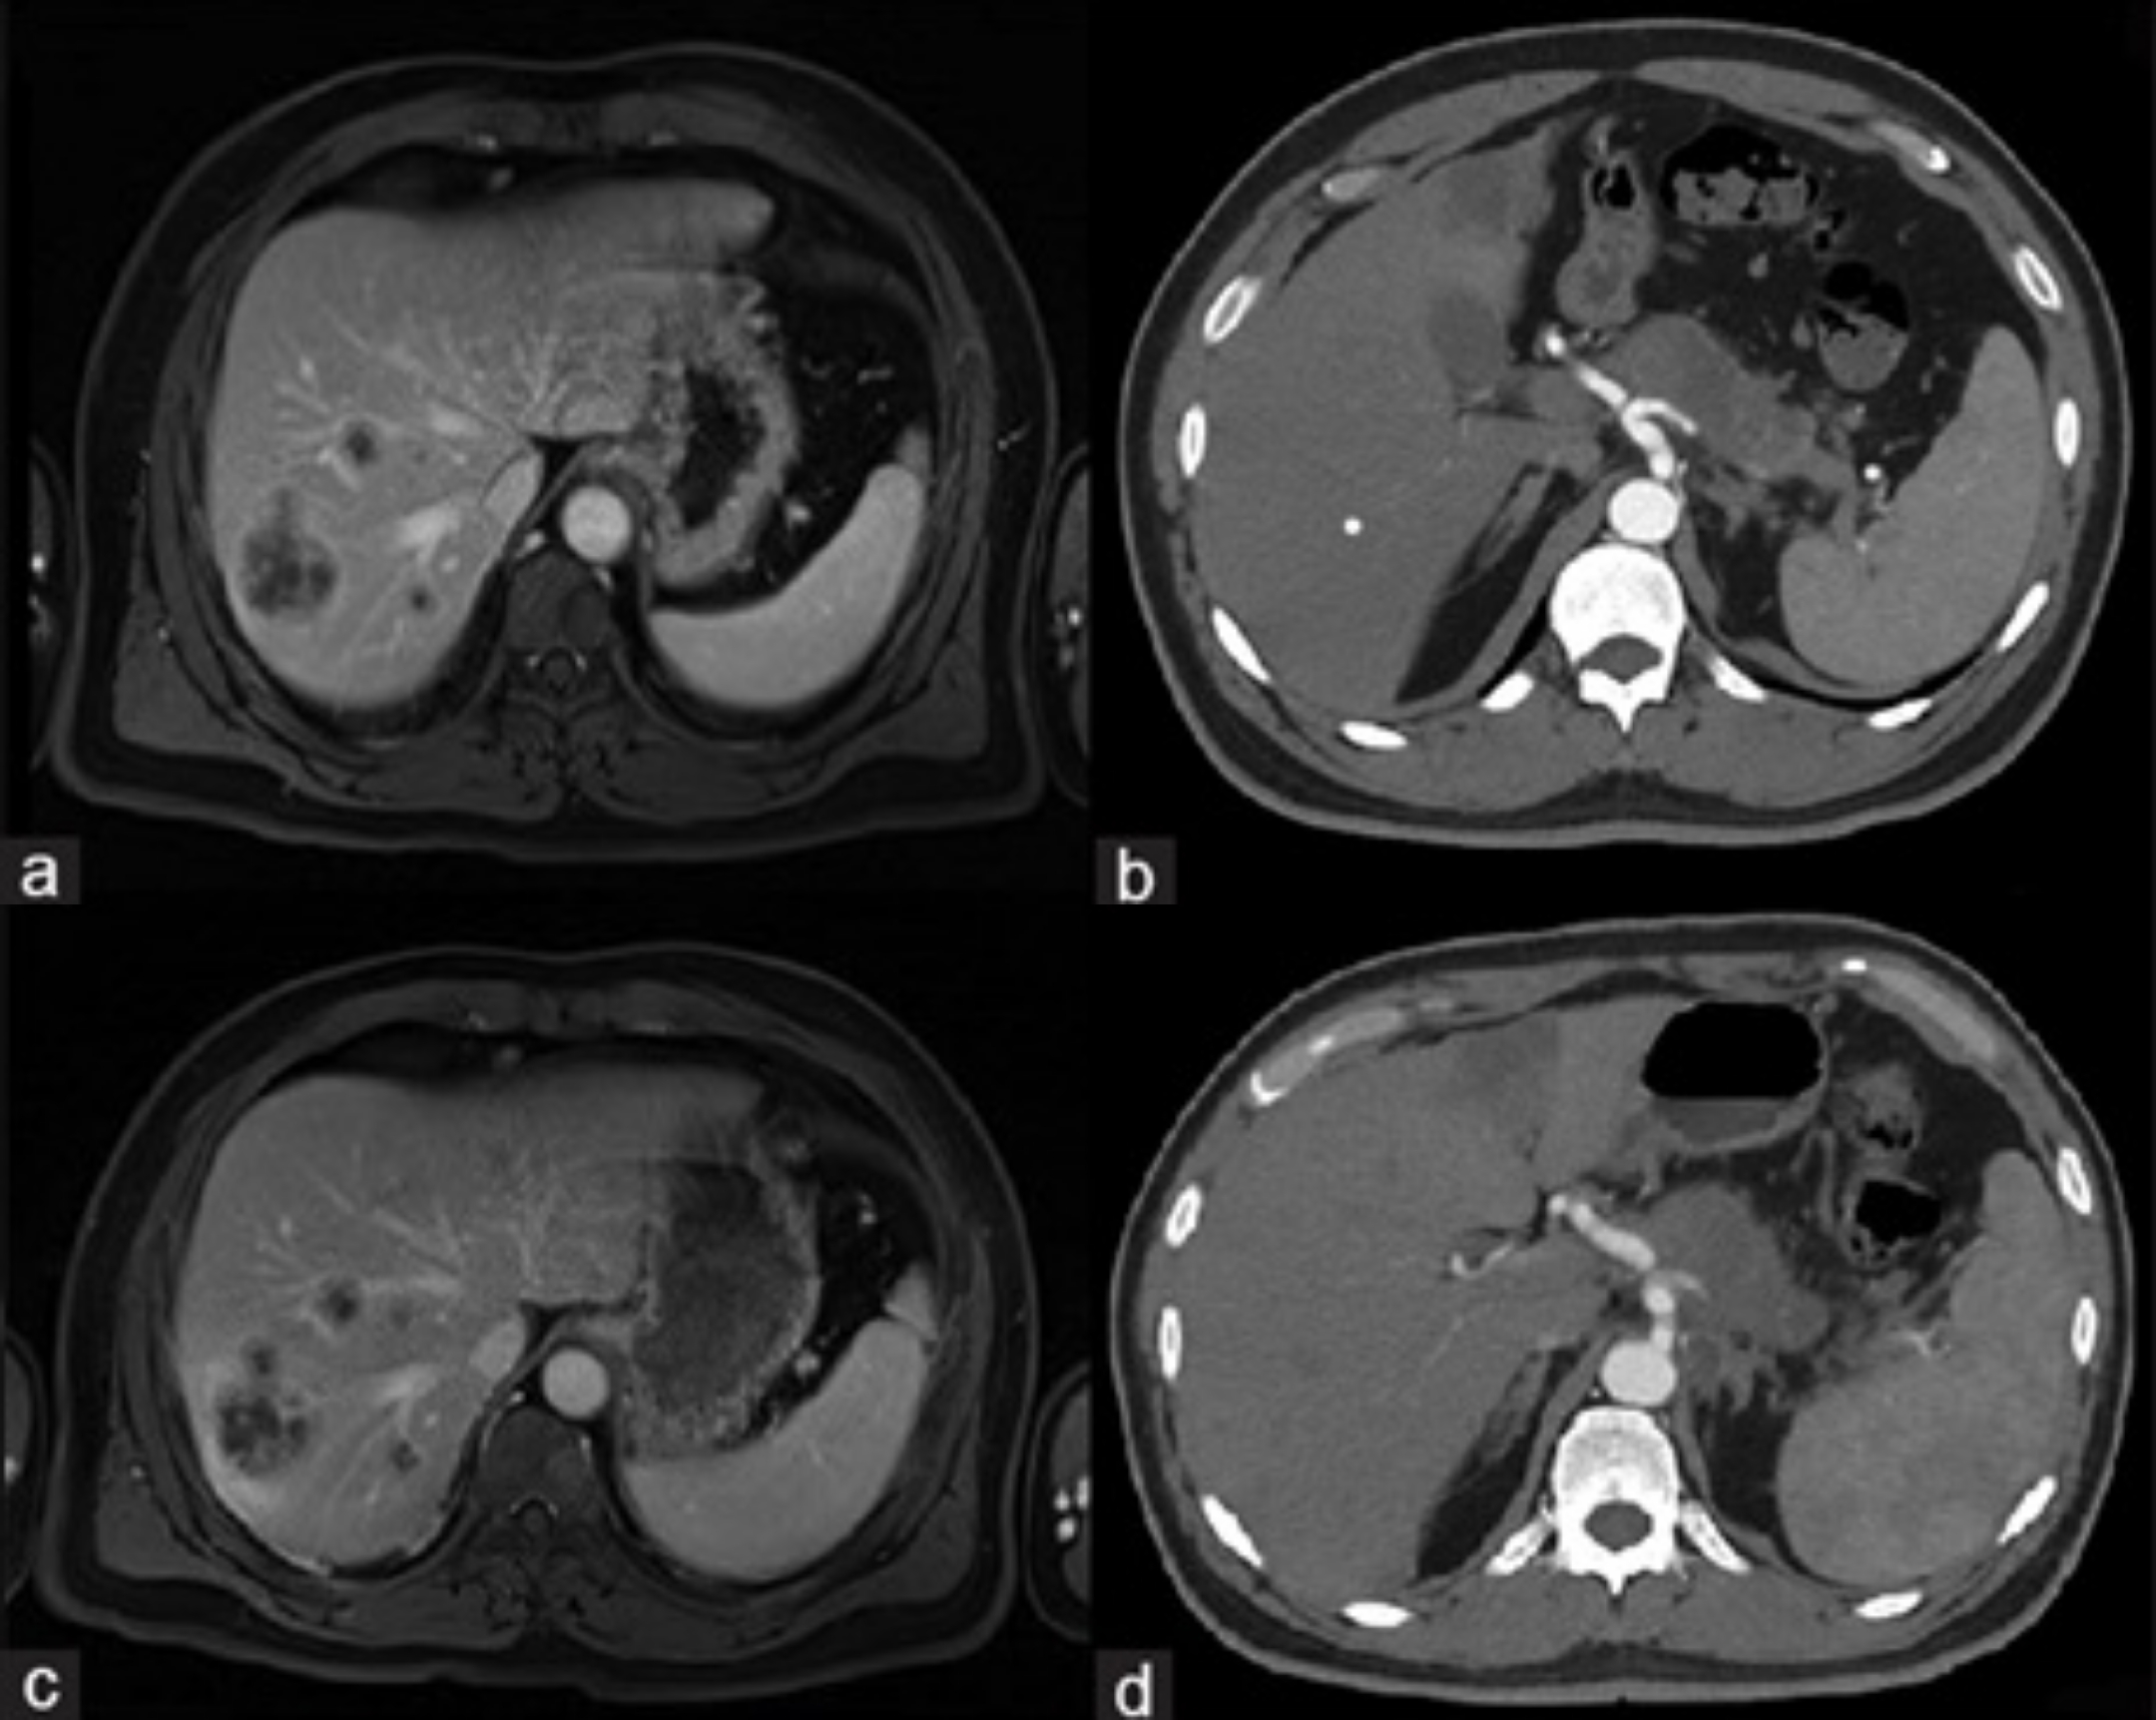

近日,ImmunityBio公布了一种现成的同种异体CD19嵌合抗原受体自然杀伤细胞疗法(CAR-NK)的QUILT-106临床研究(NCT06334991)的更新数据:数据显示持续完全缓解,缓解持续时间已延长至15个月且仍在持续,至今观察到100%的疾病控制。

1月16日,ImmunityBio公布了正在进行的QUILT-106临床研究(试验编号NCT06334991)的最新疗效与安全性数据。该研究评估的是一种现成型同种异体CD19嵌合抗原受体自然杀伤细胞疗法。该CD19 t-haNK疗法是一种靶向高亲和力自然杀伤细胞疗法,通过基因工程改造表达CD19特异性嵌合抗原受体,联合...